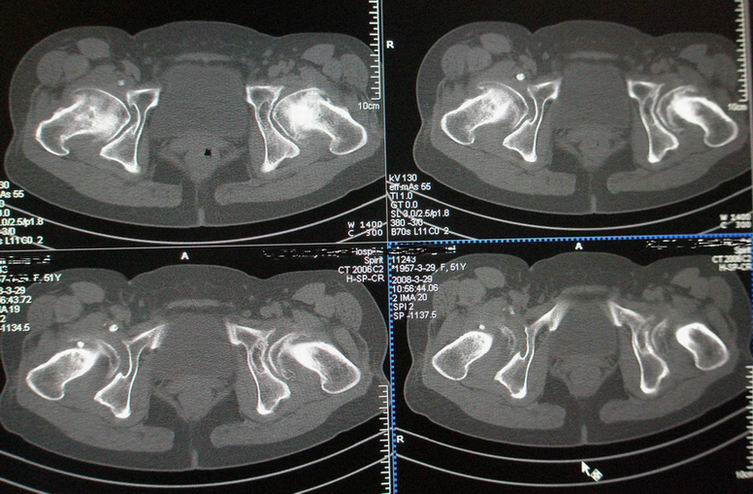

标题: CT12535:女,51岁.双髋痛多年,近加重,左腿难伸直. [打印本页]

标题: CT12535:女,51岁.双髋痛多年,近加重,左腿难伸直.

双髋无菌坏死(重度)??

先天性髋臼发育不良性骨病。双侧股骨头改变为继发性退变。

成人髋臼发育不良性骨关节病.是由于髋臼先天发育不良、髋臼角变大,部分股骨头位于髋臼以外,持重部位少,长期站立、负重造成髋臼退行性骨关节病,主要x线表现是:髋臼变浅平,髋臼角增大,ce角小于30度,髋关节骨性关节面增生硬化,关节间隙变窄,髋臼及股骨头可有囊变.但股骨头变形轻微,与股骨头坏死相比,预后好,可两三年变化不大,而股骨头坏死早期关节间隙不窄或增宽,等到间隙变窄时股骨头已明显变形.

鉴别:股骨头缺血坏死

髋关节创伤性骨关节炎

(双侧股骨头变形明显,但坏死、囊变不明显)

既然双髋疼痛多年,不会是第一次检查吧,病人以前的诊断资料能否提供,病人的其他关节都正常吗?有没有东北地区居住史?首先考虑成人股骨头无菌坏死ⅴ期,其次要考虑大骨节病。